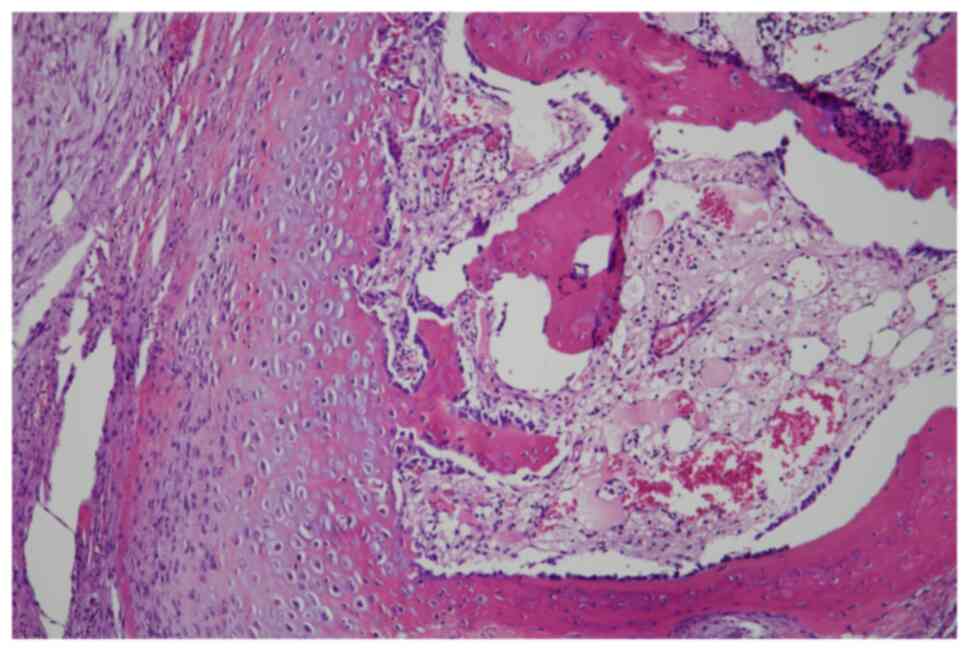

In June 2007, a 50-year-old male presented to the Masaryk Memorial Cancer Institute Sarcoma Center, with a 1-month history of persistent pain in the right ankle. Further investigations showed a cystic lesion of the talus on a CR scan, which was later confirmed by a supplementary CT scan (Fig. 16). The histopathology report diagnosed GCTB with a secondary aneurysmal cyst of the talus (Fig. 17), leading to a recommendation for intralesional resection with bone cement augmentation. After receiving the recommended treatment, the patient returned 5 months later with swelling and increased pain in the ankle. A follow-up CT scan showed destruction of the bone surrounding the bone cement, as well as osteolysis of the calcaneus and the presence of an extraosseous mass proximally (Figs. 16 and 18). Due to the extent of osteolysis, the patient required an astragalectomy. Subsequent histopathology reports showed a diagnosis of giant-cell rich osteosarcoma, contradicting the initial findings (Fig. 19). Further staging scans indicated the presence of lung metastases (Fig. 20). The Musculoskeletal Tumor Committee recommended metastasectomy followed by adjuvant CHT. Despite the successful removal of 12 lung metastases, the patient developed additional lung metastases within two months. Despite palliative care efforts, the patient died 6 months later.

Case 4. Hematoxylin and eosin staining of an open biopsy. Magnification, ×100. Fragmented biopsy of giant-cell tumor of bone without malignant features, joined by lamellae of fibrous tissue, foci of hemorrhage and solitary granules of hemosiderotic pigmentation.

Case 4. Hematoxylin and eosin staining of the resected talus. Magnification, ×100. A highly cellular malignancy was shown characterized by eosinophilic lace-like osteoid interwoven with numerous giant multinucleated cells, consistent with giant cell-rich osteosarcoma.